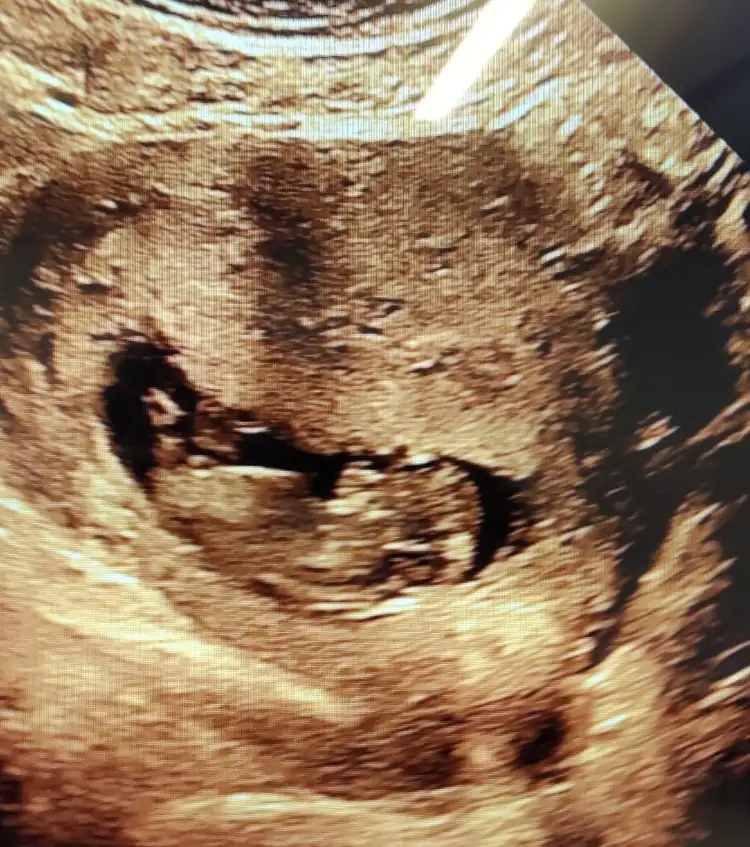

Kız görünüyorCinsiyete bakabilir misinIkra meyra 11+4 günlük sizce ne olabilir l